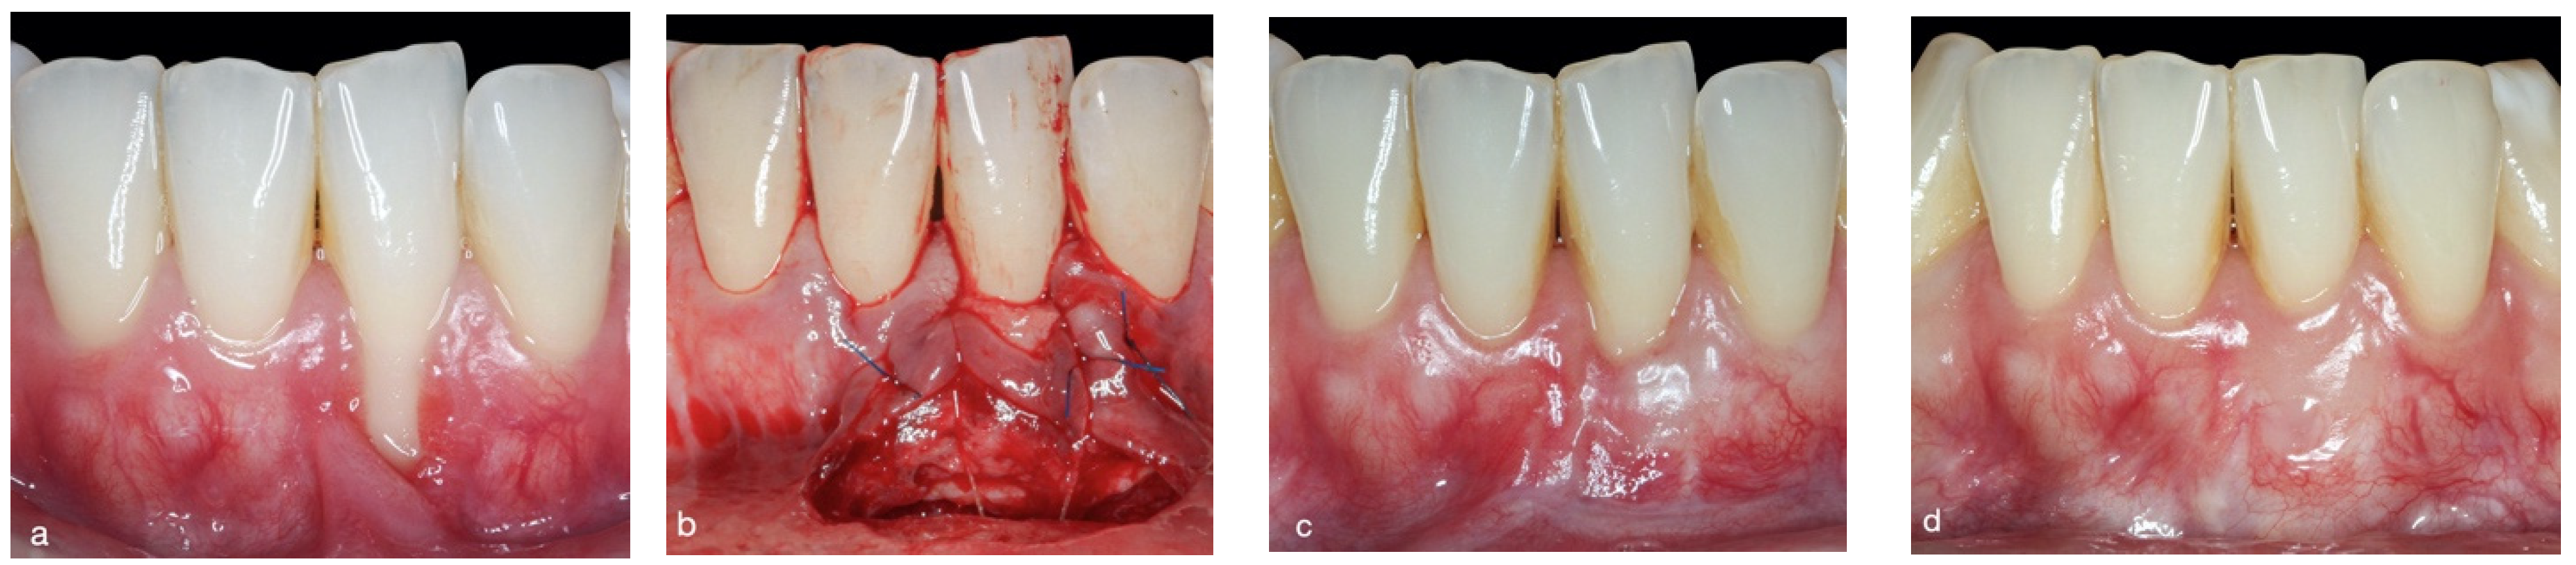

2.3. Surgical Approach